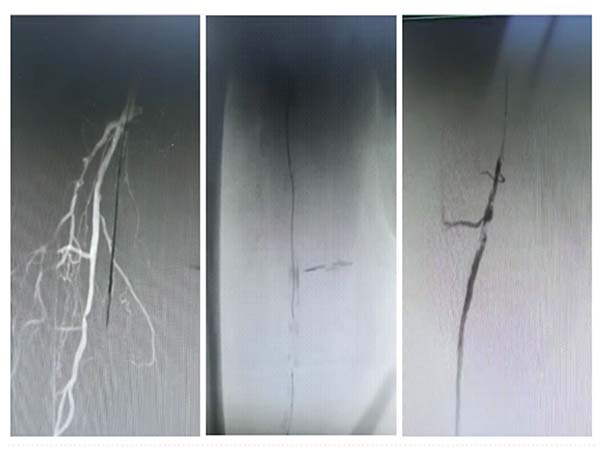

手术效果立竿见影。术后造影清晰显示,患者闭塞的下肢动脉彻底打通,血运恢复通畅,缺血症状当即缓解。术后患者下肢疼痛快速减轻,皮温明显回升,足背动脉搏动恢复,经后续治疗已能轻松行走数百米。

值得一提的是,在刘奶奶手术成功后的第三天,南院血管外科医疗团队再传捷报。他们为一名60多岁、右足足趾破溃变黑,且患有双侧股浅动脉中度节段性狭窄及闭塞的患者,成功实施了该项手术。随着下肢血运状况的改善,再辅以专业的创面处理,患者足部溃疡迅速愈合,在住院10天后顺利出院。